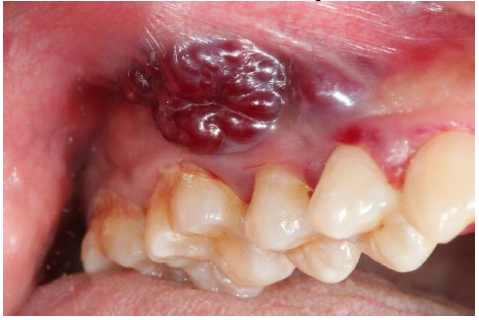

Paciente do sexo feminino, 33 anos, portadora do

vírus HIV, buscou o serviço odontológico queixandose de um inchaço de cor enegrecida em sua gengiva,

a paciente relatou não ser dolorosa e nem sentir

coceira ou formigamento na região. Após analise

clínica, observou-se a seguinte lesão:

Qual provável diagnóstico?